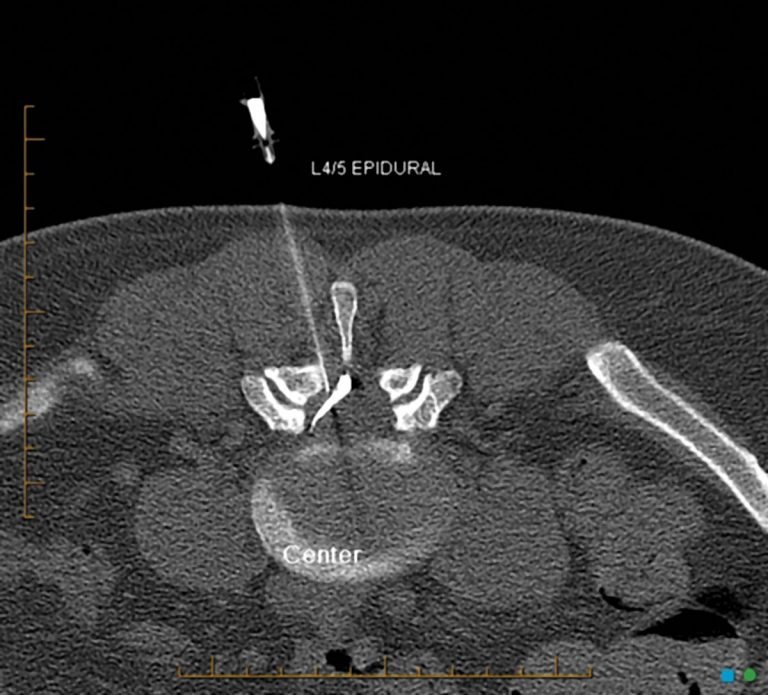

Typically, cortisone shots include a corticosteroid medication to relieve pain and inflammation over time and an anesthetic to provide immediate pain relief. Epidural steroid injection (esi) has been used as a treatment for low back pain for over 50 years. Esi is not the same as epidural anesthesia given just before childbirth or certain types of surgery.

Epidural steroid injections are commonly used to treat back pain caused by a herniated disc (slipped disc), lumbar radiculopathy, spinal stenosis or sciatica. In the last 10 to 15 years, there has been a significant increase in the use of esis for the treatment of low back pain and radicular pain without clear improvements in outcomes. But why are they so effective?